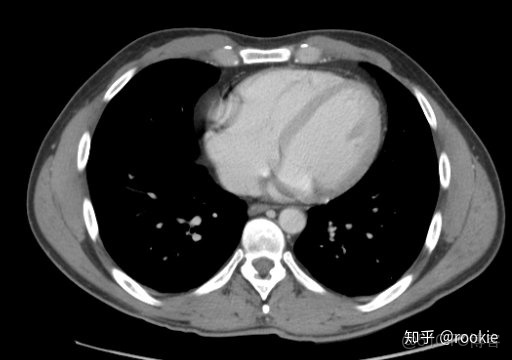

縱隔窗口窗口設置: (W:500,L:50)優點: 這些設置在本質上與軟組織設置或腹部設置相似,並進行了微調,以儘可能清晰地顯示出縱隔病理。

CLAHE算法增強局部對比度的X光圖像增強效果對比_#python 計算對比度_13

縱隔窗與腹部或軟組織窗相似,但稍作調整以顯示縱隔結構。